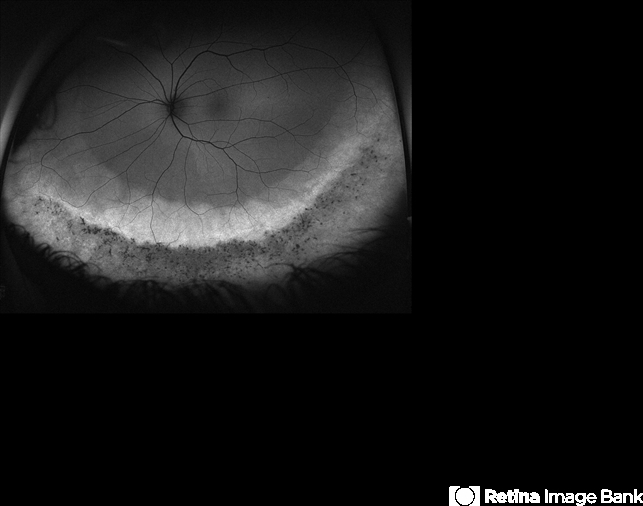

- fundus autofluorescence (FAF), Optos, ultra-wide field imaging, left eye, inferior retina, hyperautofluorescence, hypoautofluorescence

- Ultra-widefield fundus autofluorescence image of an 44-year-old male with pigmentary retinal dystrophy affecting both eyes. He presented with decreased night vision for 6 months prior to his appointment. He stated that his recovery time from transitioning from dark to light areas is reduced. He stated that his peripheral vision has never been very good for most of his life. He admits to environmental hearing loss. Patient denies family history of blin. His vision was 20/20 in both eyes. His full field ERG, visual fields were not consistent with RP. Genetic testing with ID Your IRD and annual follow up has been recommended.